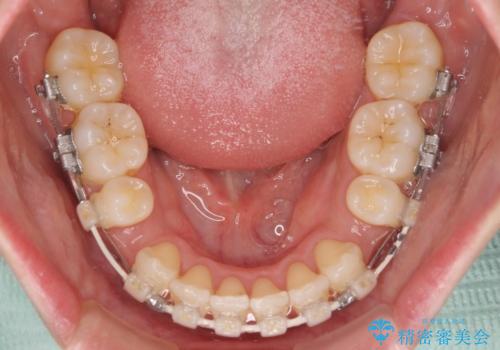

- 審美装置

舌の突出癖を改善するためのトレーニングをしっかりと行っていただいたことで、比較的スムーズに治療を進めることができました。

口元の突出感もしっかりと改善することができました。